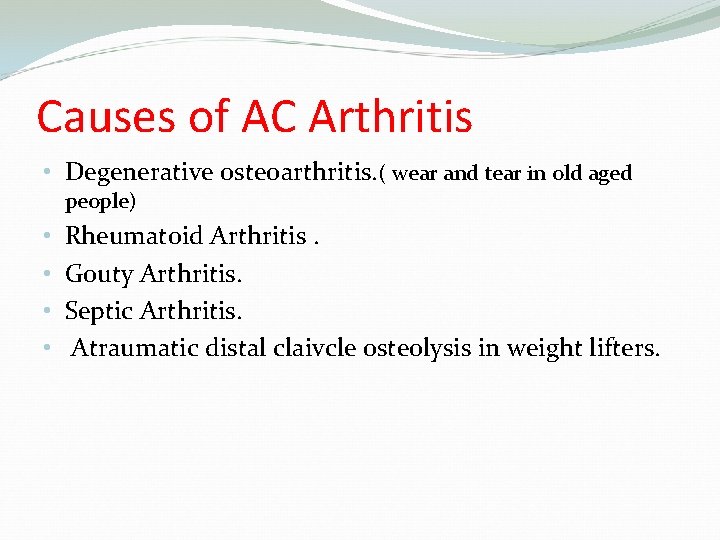

Causes of AC Arthritis • Degenerative osteoarthritis. ( wear and tear in old aged people) • • Rheumatoid Arthritis. Gouty Arthritis. Septic Arthritis. Atraumatic distal claivcle osteolysis in weight lifters.

Causes of AC osteoarthritis Degenerative osteoarthritis. ( wear and tear in old aged people) • Rheumatoid Arthritis • Gouty Arthritis • Septic Arthritis • Atraumatic osteolysis in weight lifters. ( result of repeated movements that wear away the cartilage surface found at the acromioclavicular joint) • Post-traumatic osteolysis of lateral end of clavicle. ( like dislocation or a fracture)